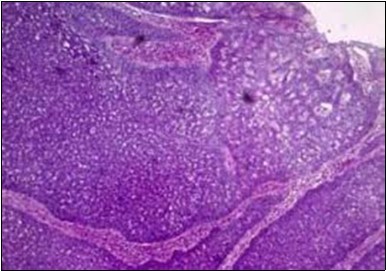

Granular arrangement of malignant cells and intercellular bridges are conspicuous with the demonstration of nuclear atypia, pleomorphism, prominent mitosis and tumour necrosis. A peripheral palisade is discernible within the cellular aggregates. Mitotic figures are common and can be quantified as up to 12 mitosis/ high power field. Tumour differentiation can prominently be of the ductal category with the demonstration of intra-cytoplasmic lumina. Comedo type tumour necrosis is evident along with foci of squamous differentiation The neoplasm is reactive to periodic acid Schiff ‘s (PAS) stain. (Figure 1, Figure 2, Figure 3, Figure 4, Figure 5, Figure 6, Figure 7, Figure 8, Figure 9, Figure 10, Figure 11, Figure 12, Figure 13.

Figure 3.Cohesive accumulations with numerous ductular articulations of carcinoma cells in eccrine porocarcinoma (15).